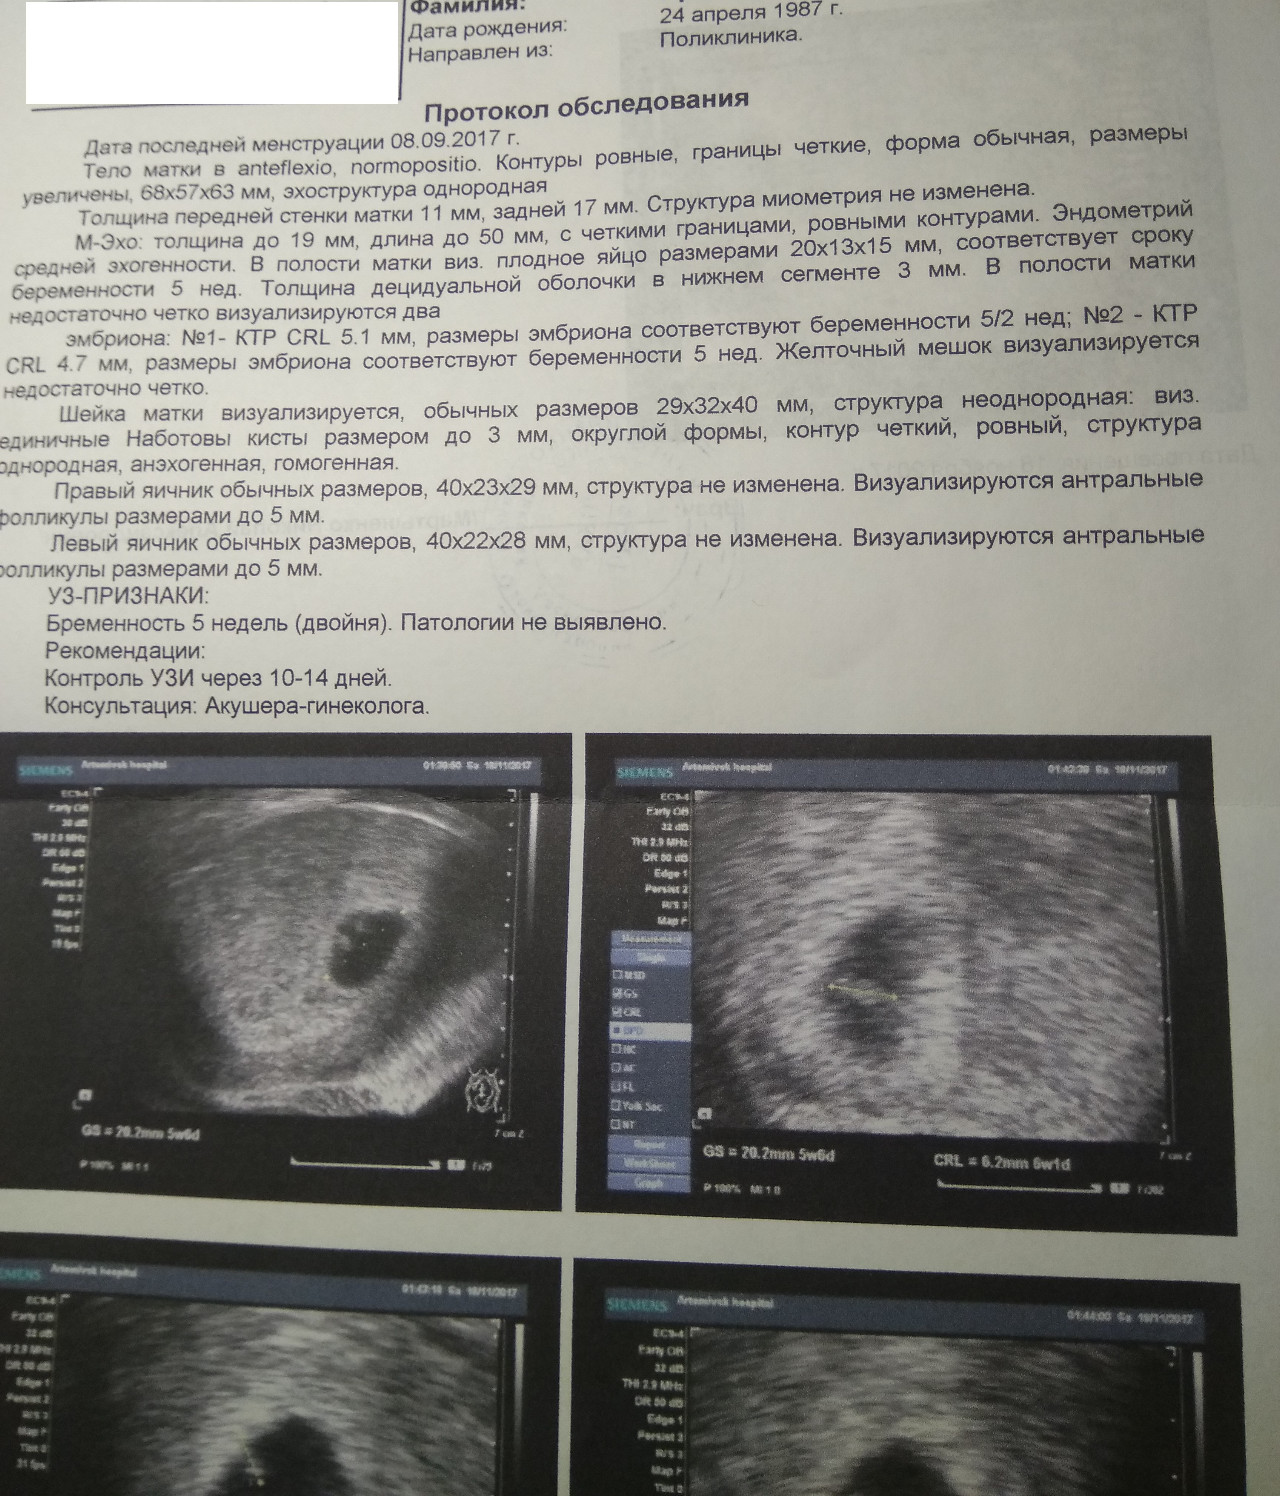

Развитие эмбриона на 8 неделе беременности